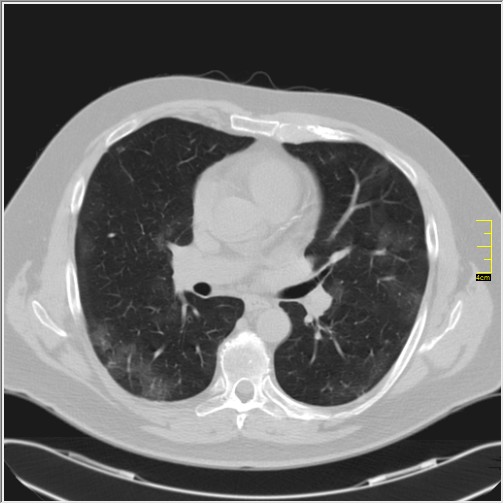

Četiri dana kasnije. Isti pacijent dolazi sa istim pulmologom. Situacija je sada sasvim drugačija. Temperatura 39.5 C. Saturacija 92. Laboratorija daleko gora. Uradim CT pluća. Ovo je izašlo.

Severity score 15/25. Pacijent je upućen na bolničko lečenje.

Ono što zbunjuje, a to se ponavlja zadnjih 10 dana, je da fibroza nastupa u progresivnoj fazi, znači na početku bolesti. Toga nije bilo do sada. Sledećih dana ću o tome.

Ovo je samo 4 dana. Od zdravlja do teške bolesti. Pacijent je 45 godina starosti, očigledno nije povećane težine, kaže za sebe da je bio sportista. U anamnezi nije naveo nikakve bitne bolesti.